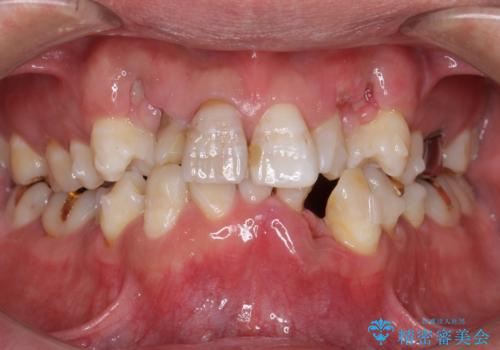

重度の叢生(歯並びのがたがた)のため、

①小臼歯抜歯でしっかりと歯並びを整える矯正治療

②前歯のセラミック治療を行いやすくするための補綴前矯正

患者様の「できるだけ短期間で治療を終わらせたい、セラミックが入れられたら良いので大がかりなことはしたくない」とのご要望により、3Dシミュレーションを何度も行い患者様とのコンサルを重ね、上顎左右犬歯と左下2を抜歯して②のプランである補綴前矯正(インビザライン)を行うことにしました。

寿命が長く機能的に重要な役目を果たす犬歯を抜くリスクや、矯正治療の仕上がりに限界があることをご理解頂いた上で治療を行っております。